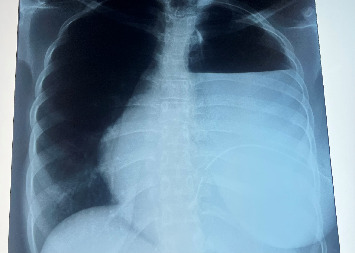

Background: Our case highlights the challenges in diagnosing and managing achalasia cardia, particularly in resource-limited settings and more so in adolescents who fall outside of the typical age range. Case Presentation: We present a case of an 18-year-old female from Uganda who was admitted with a 6-month history of progressive dysphagia, weight loss, and postprandial vomiting. Diagnosis of achalasia cardia was confirmed via endoscopy and barium swallow. Heller cardiomyotomy via open transthoracic approach was performed, but she developed an esophageal perforation, which was successfully managed with repeat thoracotomy and esophageal repair. Complete resolution of achalasia symptoms was achieved at a 5-month follow-up. Conclusion: This case highlights the importance of maintaining a high index of clinical suspicion, especially in young patients, and the significance of informed consent prior to initiating treatment. Additionally, it emphasizes the importance of early recognition of treatment-related complications, such as esophageal perforation, as key to prompt management and improved patient outcomes.